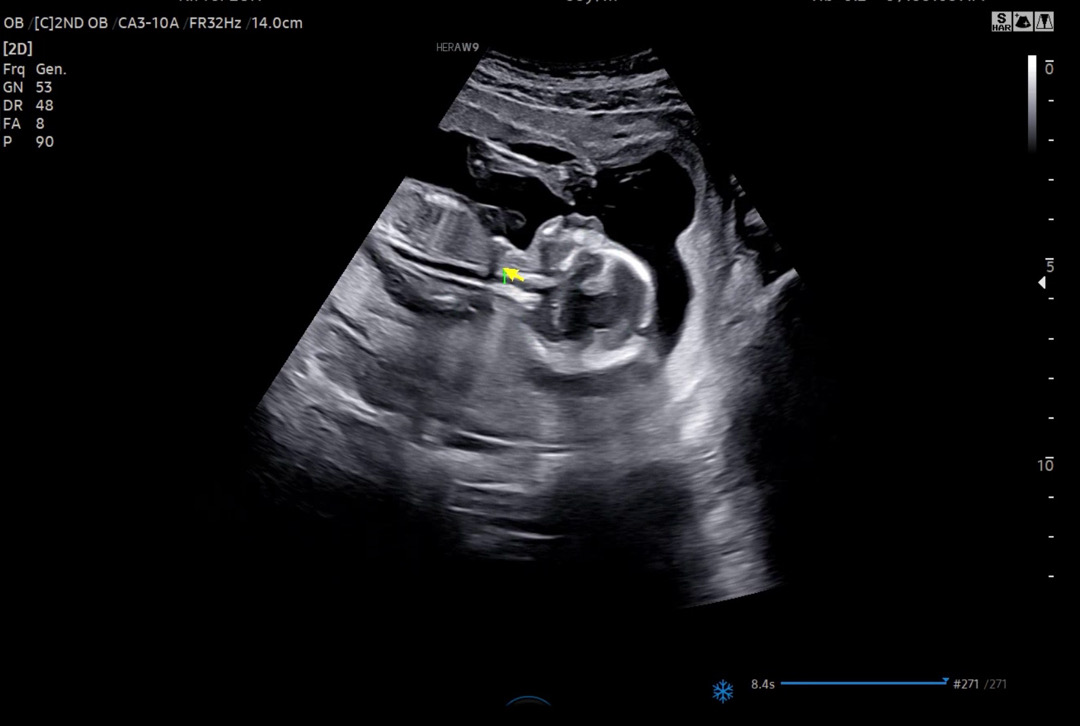

손가락 먹는 울애기보고가세여~💙

4주를 기다려 16주 0일에 찌뇽이보고왔어요:) 임신 증세가 하나도 없어 잘 있는건가.... 넘 궁금했는데 발차기도 하고 손가락도 쫍쫍 하고 있는 잘 놀고있는 울애기보니까 감동 그 자체ㅠㅠㅠ 춈파 끝에도 성별말안해주시길래 다급하게 성별궁금하다고 하니까 공주님~💕 이라고 ㅎㅎㅎ 딸이어도 아들이어도 서운했을거같은데 이왕 딸 맘인거 즐기고 열심히 핑크템 준비해야겠어요! 찌뇽이 보러 와주신 맘님들 새해복 더 많이 받으세요~~:)

꺄! 손 빨면서 젖 빠는 연습하는거라고 하더니 초음파로 딱 찍혔네요!! 넘 귀여워요♡